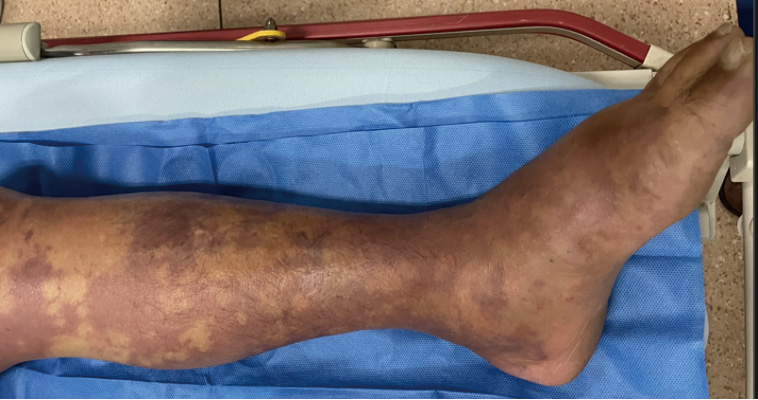

4 临床表现创伤弧菌脓毒症临床亚型有原发性脓毒症、创伤感染、胃肠炎型和其他类型[12, 51]。原发性脓毒症常见于生食牡蛎等贝壳类海鲜后,病原体通过胃肠道入血[52]。创伤感染一般由身体原有创口接触带菌海水或被海生动物刺伤而感染[53]。可出现典型的创伤弧菌坏死性软组织感染(Vv-NSTIs),严重者病情进展迅速,数小时内即可发展为脓毒性休克和MODS,危急生命[54]。局部表现:早期皮肤症状可不典型,随着病情进展,局部症状明显并出现斑丘疹、荨麻疹、多行性红斑和蜂窝织炎、小水泡或血泡[54]。当组织坏死时出现大片瘀斑(图 1)、张力升高、水泡或血泡(图 2)、坏死破溃、皮下捻发感、皮肤发黑,病灶范围扩大蔓延可累及多个肢体[55-58]。一项回顾性研究分析了10年共85例创伤弧菌感染患者,其中出血性大泡性皮肤病变、坏死性筋膜炎、涉及两个或多个肢体的皮肤软组织感染是影响患者预后的独立危险因素[23]。全身表现:严重者出现多器官功能衰竭,除发热、心动过速、低血压、休克等表现外,也可出现呼吸急促、呼吸困难、少尿、无尿、黄疸等相应脏器损伤的表现。

| 图 1 典型肢体表现(瘀斑) |

推荐意见2:创伤弧菌坏死性软组织感染可迅速进展至脓毒性休克和多器官功能衰竭阶段,皮肤瘀斑、血泡等表现提示出现软组织感染及坏死。(证据等级Ⅰ级,推荐强度A)